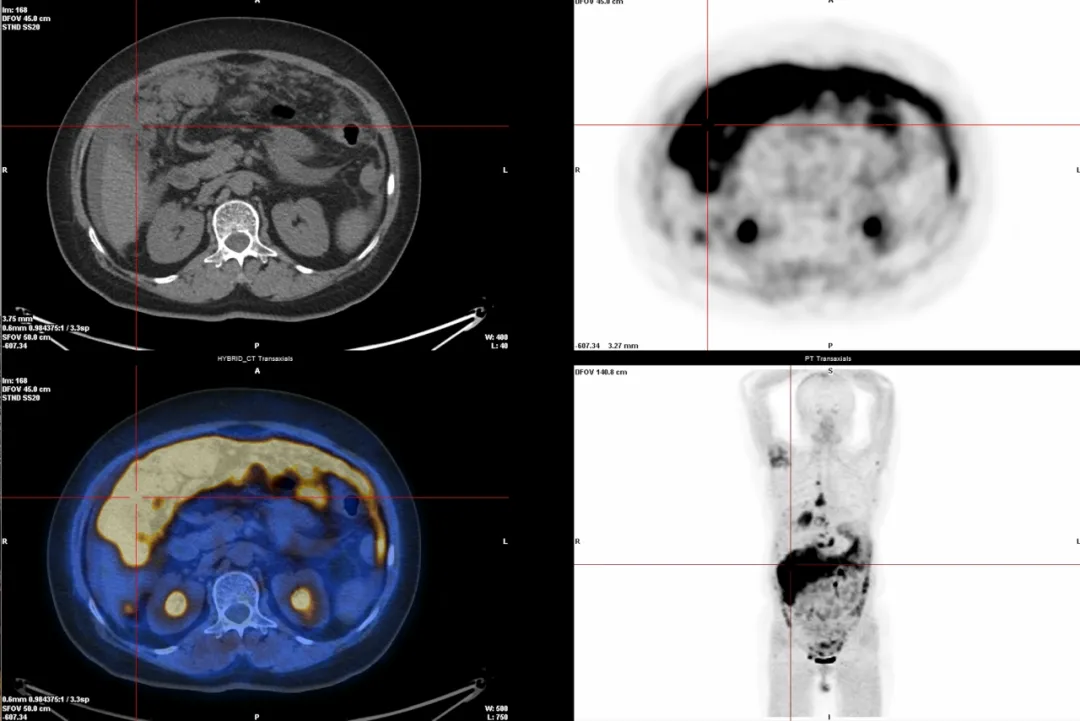

△前列腺癌微小原发灶检测

2.多种癌症检查(68Ga-FAPI):能检测很多种癌症,尤其是肝癌、胃肠印戒细胞癌、腹膜转移癌等,因为它能精准找到肿瘤周围的特殊细胞(成纤维细胞)。